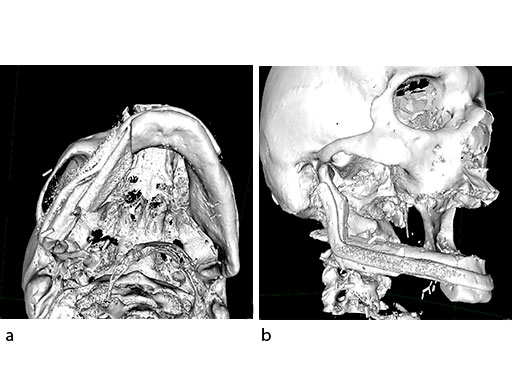

Virtual surgical planning using preoperative CT DICOM datasets of the defective CMF region, and the donor region from where the bone flap will be harvested, provides a detailed outline of the bony framework (eg, an autogenous neomandibular section consisting of an array of fibular segments).

The design of the bony segments and the overall framework is defined in an interactive planning session between the surgeon and a medical engineer. In oncologic surgery, a primary reconstruction is preceded by a virtual tumor resection for exact matching of the defect and the bony restoration. In secondary reconstruction, it will often be necessary to reposition collapsed bony remnants and to level their cut edges in order to define the real extent of the preexisting defect. Patient specific plates for the mandible have the versatility to bridge almost all defect patterns in the mandible (Fig 1abc). After exarticulation of a condyle, they are even compatible with the Matrix Mandible condylar head add-ons as a joint component for temporary replacement. The cutting guides, templates, and the patient specific mandibular reconstruction plates can be supplemented with stereolithographic (STL) models of the mandible, displaying the defect and the composed fibular segments as either a hybrid or as separate items. In the separate format, the models are an ideal instrument for double-checking. The defect size and the correct placement of the patient specific plates for the mandible are controlled by inserting the STL fibular segment assembly in situ. On a side table, the fitting of the real fibular segments into the defect of the STL model can be assessed.

At this stage, future dental implant insertion requires an alveolar process in a lingual shift position. To this end, the anterior segment is aligned with a medial offset. The posterior segment, which replaces the angle/anterior ramus region, is arranged with an overlapping zone. The inner cortex of the posterior segment in the area of intersection is trimmed to keep the restoration within the bounds of the original width of the angle. This results in a sort of "bayonet connection". The basal border of the mandibular body is not built up, since it is not functionally relevant.

With the design of the bony framework being ready, the reconstruction plate is molded to the geometry of the outer surface of the neomandibular division. The plate profile (thickness 2.0 or 2.5 mm) is chosen and the plate screw hole pattern is customized. Relative to the osteotomy sites, the fibular segment configuration, and the adjacent native bone, the number, position, and angulation (up to 15) of the plate screw holes is specified with respect to overall stability. A defined screw hole position facilitates accessibility for screw insertion and avoids interference with nerves, tooth roots, osteotomy interfaces, and existing/future implants.